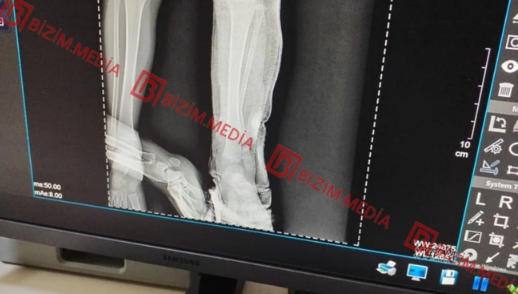

Şikayətçinin sözlərinə görə ilk dəfə 2022-ci ilin iyulunda qızının qolunda yanıq izləri görüb. Məlum olub ki, isti qaşığı 5 yerdən uşağın qoluna basıb və I dərəcəli termiki yanıq yetirib:

"Bundan başqa, müxtəlif vaxtlarda – 2023 və 2024-cü illərdə dəfələrlə taxta əşya ilə döyərək sifətinə və yanaq nahiyəsinə xəsarətlər yetirib. İndiyədək azyaşlı qızıma əziyyət verir. Digər kiçik qızıma da ehtimal ki, eyni davranışı sərgiləyir. Hər iki övladımın psixoloji durumu korlanıb. Bu azmış kimi uşaqları nəzarətsiz buraxır. Bu yaxınlarda kiçik qızımı avtomobil vurub, amma qadın bizi aldadaraq evdə yıxıldığını deyib. Kiçik qızımın ayağının biri qırılıb, yeriyə bilmir, gipsdədir və uzun müddət müalicəyə ehtiyacı var".

Baxmayaraq ki, Lənkəran Məhkəmə-Tibbi Ekspertiza Mərkəzinin rəyində uşağın qoluna isti metalla (qaşıq) dağ çəkilməsi inkar olunmur.